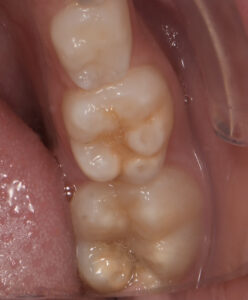

Le congrès de l’EAPD (Académie Européenne d’Odontologie Pédiatrique) a défini des critères de diagnostic en 2003. A savoir des opacités délimités, des fractures post-éruptives, des restaurations atypiques ainsi que que des extractions des molaires. (3) Le diagnostic différentiel doit surtout s’établir entre des amélogénèses imparfaites et des hypominéralisations d’origine traumatique pour les dents antérieures. Cliniquement, les dents vont présenter des colorations blanches ou brunes opaques sur une partie ou sur toute la surface de la dent (Figures 1-2-3-4).

formation dentaire pédodontie Figure 1.

MIH, état des lieux et thérapeutiques Figure 2.

formation dentaire pédodontie Figure 3.

Cette atteinte peut être soit légère (émail blanc, opaque), soit modérée (coloration jaune, brune, surface crayeuse et effondrement postéruptif de l’email ou PEB) ou enfin sévère (atteintes associées à des pertes de substances importantes). De plus, l’intégrité de la dent peut être aussi touchée. Plus la MIH est sévère et plus le manque d’émail sera important donc plus les sensibilités/douleurs seront importantes aussi. Cette sévérité varie en fonction des personnes, mais également au sein des dents d’un même individu : on parle d’atteinte asymétrique. Toutes les dents ne sont pas toutes touchées de la même façon, et ne nécessiteront donc, pas les mêmes types de soin.

Figure 3-4 : Molaires atteintes de MIH (HSPM + MIH pour la figure 3)